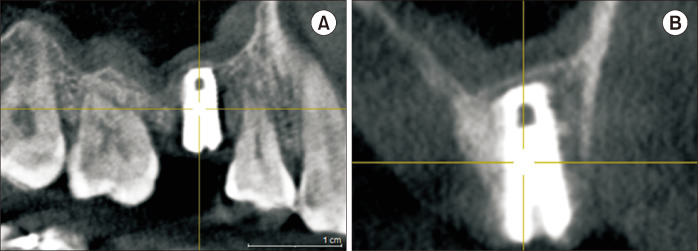

Transcrestal sinus floor elevation (tSFE) is a useful method for vertical bone augmentation in the posterior maxilla at the time of implant placement. However, this is a blind surgical technique with a risk of perforating the Schneiderian membrane. In this article, we present a simple technique to perform tSFEs using ridge spreaders. With this technique, the tSFE is performed in a slow and controlled manner without the entry of instruments into the maxillary sinus. Furthermore, many clinicians may find they already have the necessary surgical tools within their armamentarium. This precludes the need for rotary drills that spin at high revolutions per minute in the sinus cavity or osteotomes which may result in an uncomfortable patient experience. In order to fully exemplify its clinical utility in performing successful tSFE without membrane perforation, we present this surgical technique in a case with limited residual bone height and a steeply oblique sinus floor.